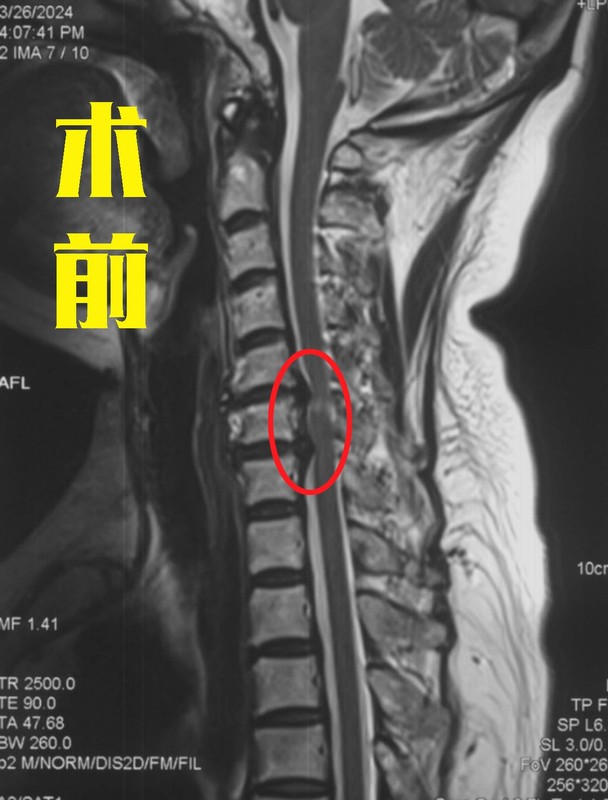

許多患者在檢查頸椎的時候,發(fā)現(xiàn)自己的報告單上寫著“頸椎間盤突出、脊髓變性”等字樣,這個時候醫(yī)生就會告知情況嚴重,需要手術!這就讓不少患者非常糾結(jié),真的就必須手術嗎?而在網(wǎng)上一查,都說脊髓變性了肯定要手術,而且術后可能還恢復不好。這是真的嗎?最近,宣武醫(yī)院王作偉主任就接診了一位62歲的女性患者。她在1年前就出現(xiàn)了右側(cè)上肢疼痛,雙下肢的酸麻、行走不穩(wěn)的情況,去了當?shù)蒯t(yī)院檢查后發(fā)現(xiàn)是脊髓型頸椎病,并告知脊髓變性了,需要盡快手術。當時她覺得自己的癥狀不是特別嚴重,就沒有立即手術,服用了一些藥物,做了保守治療。但是今年她的癥狀越來越重,行走困難,要人扶著才能走,上肢也疼痛劇烈,什么活兒也干不了。這次,家里人就很重視了,去了不少醫(yī)院,都建議她盡快手術,有的醫(yī)生還說脊髓變性了,脊髓有了一定損傷,術后可能就恢復不好了。這讓她們一家很擔心,現(xiàn)在已經(jīng)不是手術不手術的問題,而是做了手術能不能恢復的問題了。為了進一步治療,他們決定去北京大醫(yī)院再看看,最后找到了王主任。脊髓型頸椎病出現(xiàn)的脊髓變性是怎么回事?脊髓型頸椎病是頸椎病眾多類型中最危險的一型,它之所以這么危險,就是因為壓迫到脊髓。那報告當中的脊髓變性又是怎么回事?簡單來說,就是脊髓受壓久了,脊髓缺血了,這種情況持續(xù)時間長了就產(chǎn)生了脊髓變性。如果再不盡快處理,繼續(xù)發(fā)展下去就會有脊髓壞死的可能,到那個時候患者就會癱瘓。所以,一旦確診為脊髓型頸椎病后,都是建議盡快手術,避免病情向最嚴重的情況(癱瘓)繼續(xù)發(fā)展。脊髓變性在頸椎的核磁共振片子上顯示很明確,椎管內(nèi)正常的脊髓是暗黑色的一條,而脊髓變性的地方顏色呈現(xiàn)變白、變淺。就像這位患者的片子,在頸5-6、頸6-7處的椎間盤有突出,而且嚴重壓迫到了后面的脊髓,尤其是頸5-6水平處的脊髓顯示變淺,提示有脊髓變性。術前影像學資料:脊髓變性了再做手術后還能完全恢復嗎?這還是需要根據(jù)患者術前的具體情況而定,如果患者術前脊髓變性很輕、時間短,術后的各項功能還是可以恢復的;但如果患者術前脊髓受壓時間特別久,變性也很嚴重,術后的癥狀就會恢復得很慢,甚至一部分功能出現(xiàn)不可逆的損傷,這時就不能完全恢復了。但相比完全癱瘓來說,盡早手術給脊髓減壓還是非常有必要的。這位患者在了解后就馬上同意了手術,王主任根據(jù)她的具體情況為她定制了微創(chuàng)的頸前路手術,并在其后為她成功完成手術。手術中在保護周圍神經(jīng)、脊髓、血管等組織的情況下,將兩個節(jié)段的椎間盤突出切除,給脊髓進行了徹底減壓,并進行內(nèi)固定建立頸椎的穩(wěn)定性。術后,她右上肢疼痛癥狀得到很快緩解,下肢麻木也得到了一定改善,在術后三天,她已經(jīng)可以自己獨立行走了,效果很好。術后影像學資料:其實,脊髓型頸椎病只要確診了,都是需要手術的,而且早做手術要比晚做的效果好很多,有時甚至是天壤之別,所以還是建議大家能早做就早做,不要拖到后面脊髓變性得很嚴重了再做。